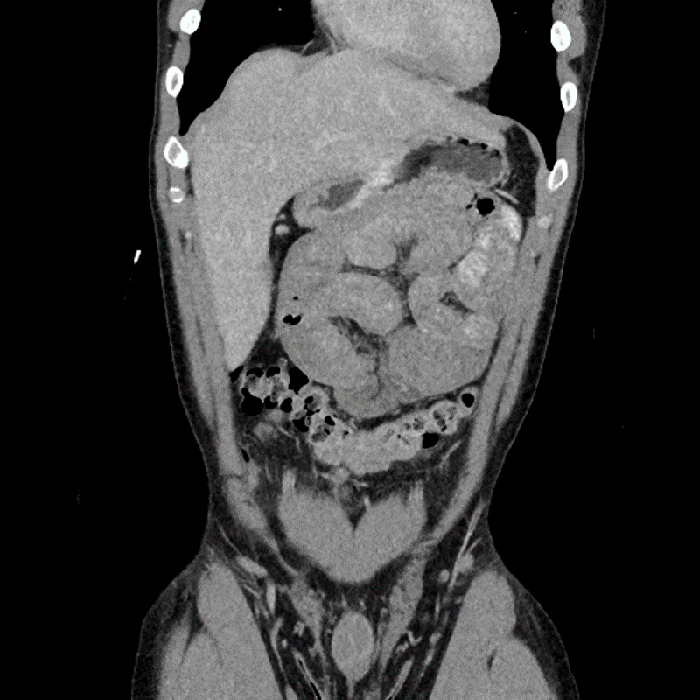

In the operating room, the case was attempted laparoscopically at first, but due to bowel dilation and torsion of the small bowel underneath the transverse mesocolon, the decision was made to convert to a laparotomy. Upon opening the abdomen, the majority of the small bowel was found to be herniated up into the lesser sac. After lysing adhesions and opening a large hernia sac, a congenital left paraduodenal hernia was identified. Bowel was reduced through the defect to its natural position inferior to the colon and the hernia sac was excised. The abdomen was then further explored with normal appearing anatomy otherwise. The paraduodenal hernia was closed using four interrupted silk sutures. The abdomen was copiously irrigated and the fascia and skin were closed primarily. Some representative images from the case can be seen below.

Unfortunately, CT evaluation of any type of internal hernia is rare in radiology literature.8 However, other case reports claim that a characteristic appearance of left PDH on CT consists of an abnormal cluster or saclike mass of dilated small bowel loops lying between the pancreas and stomach to the left of the ligament of Treitz. This usually creates a mass effect that displaces the posterior wall of the stomach, the duodenal flexure inferiorly and the transverse colon inferiorly.6,9 At the entrance of the hernia sac, the mesenteric vessels supplying the herniated small bowel segments become stretched, crowded, and engorged.10,11 CT demonstrates the inferior mesenteric vein and left colic artery as landmarks above the encapsulated bowel loops, as the anterior wall of the sac contains these vessels. Radiographic landmarks for right PDH include the superior mesenteric artery and right colic vein at the anterior-medial border of encapsulated small bowel loops.6

With the low prevalence of internal hernias overall, it is still a daunting task to identify this pathology from radiologic findings alone unless clinicians approach these scans with initial suspicion or an obvious "swirl sign" is identified. In our patient's case, when reviewing the CT in retrospect we can see that the dilated small bowel appears to be located superior to the transverse colon. However, even when viewing the sagittal imaging views, it is difficult to appreciate any passing through a mesenteric defect.